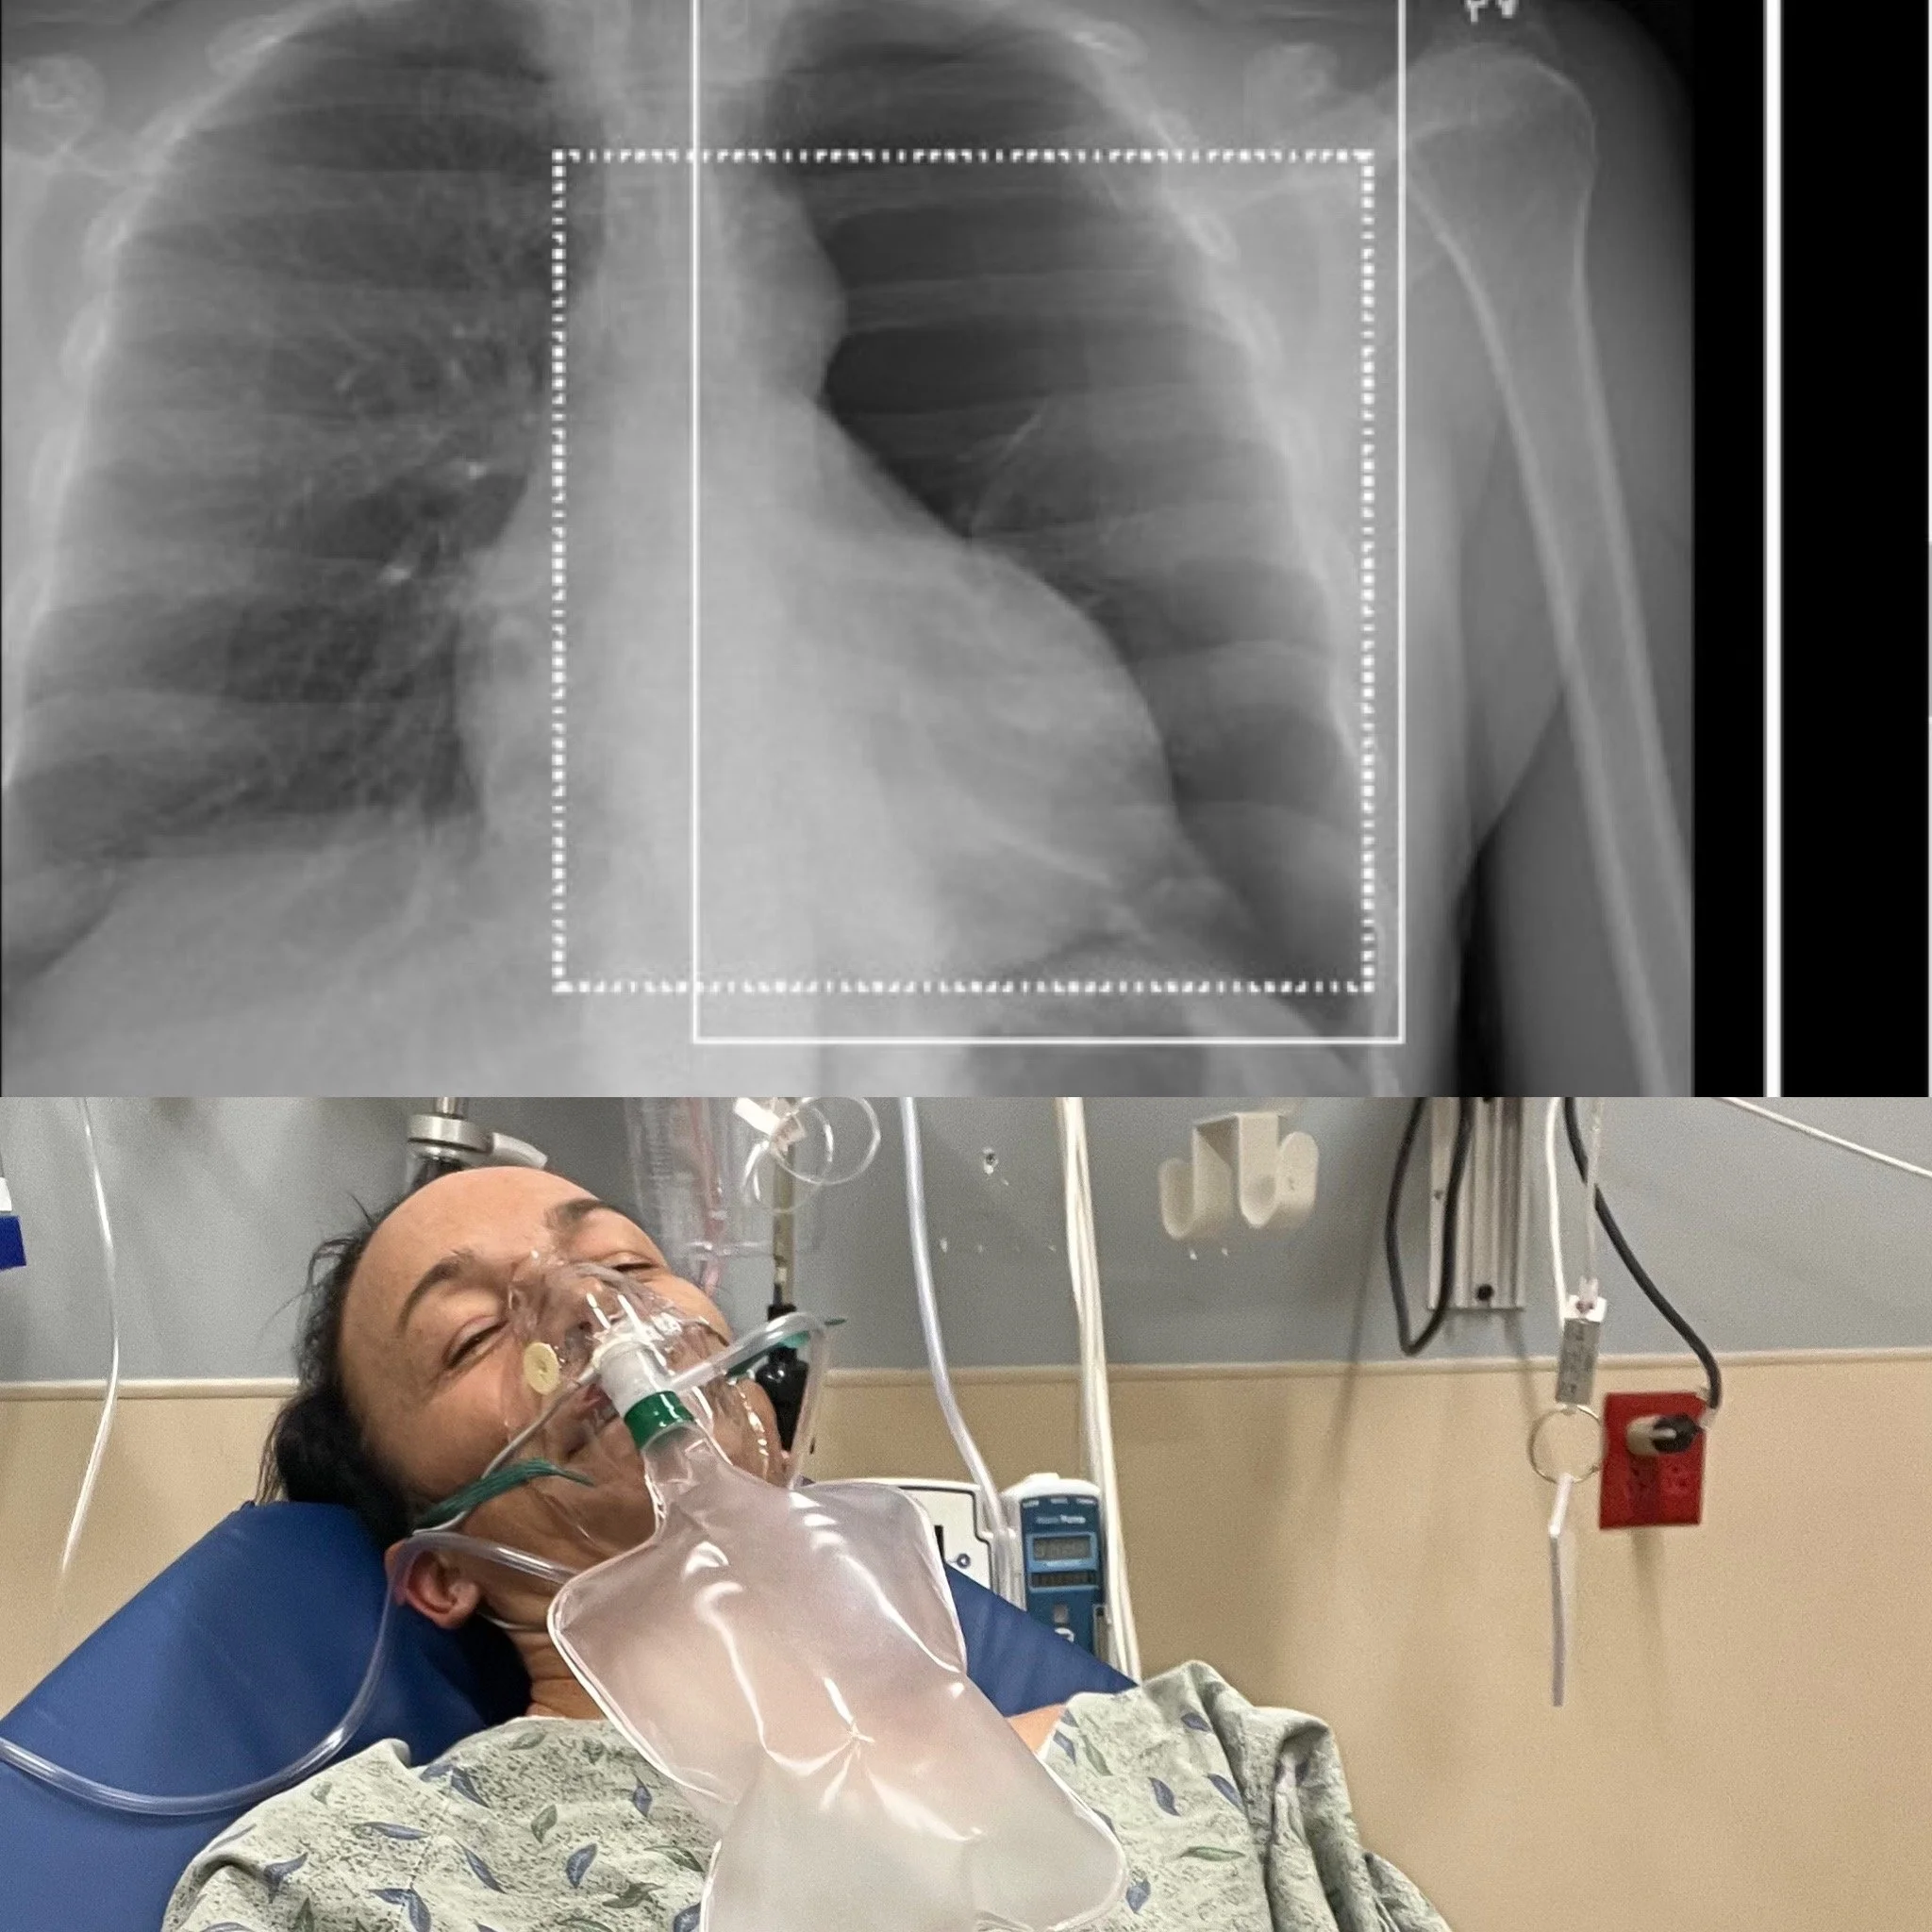

Collapsed Lung and Broken Ribs The Acute Phase Return To Sport Health, Injury Prevent & TreatMarilyn ChychotaDecember 27, 2023